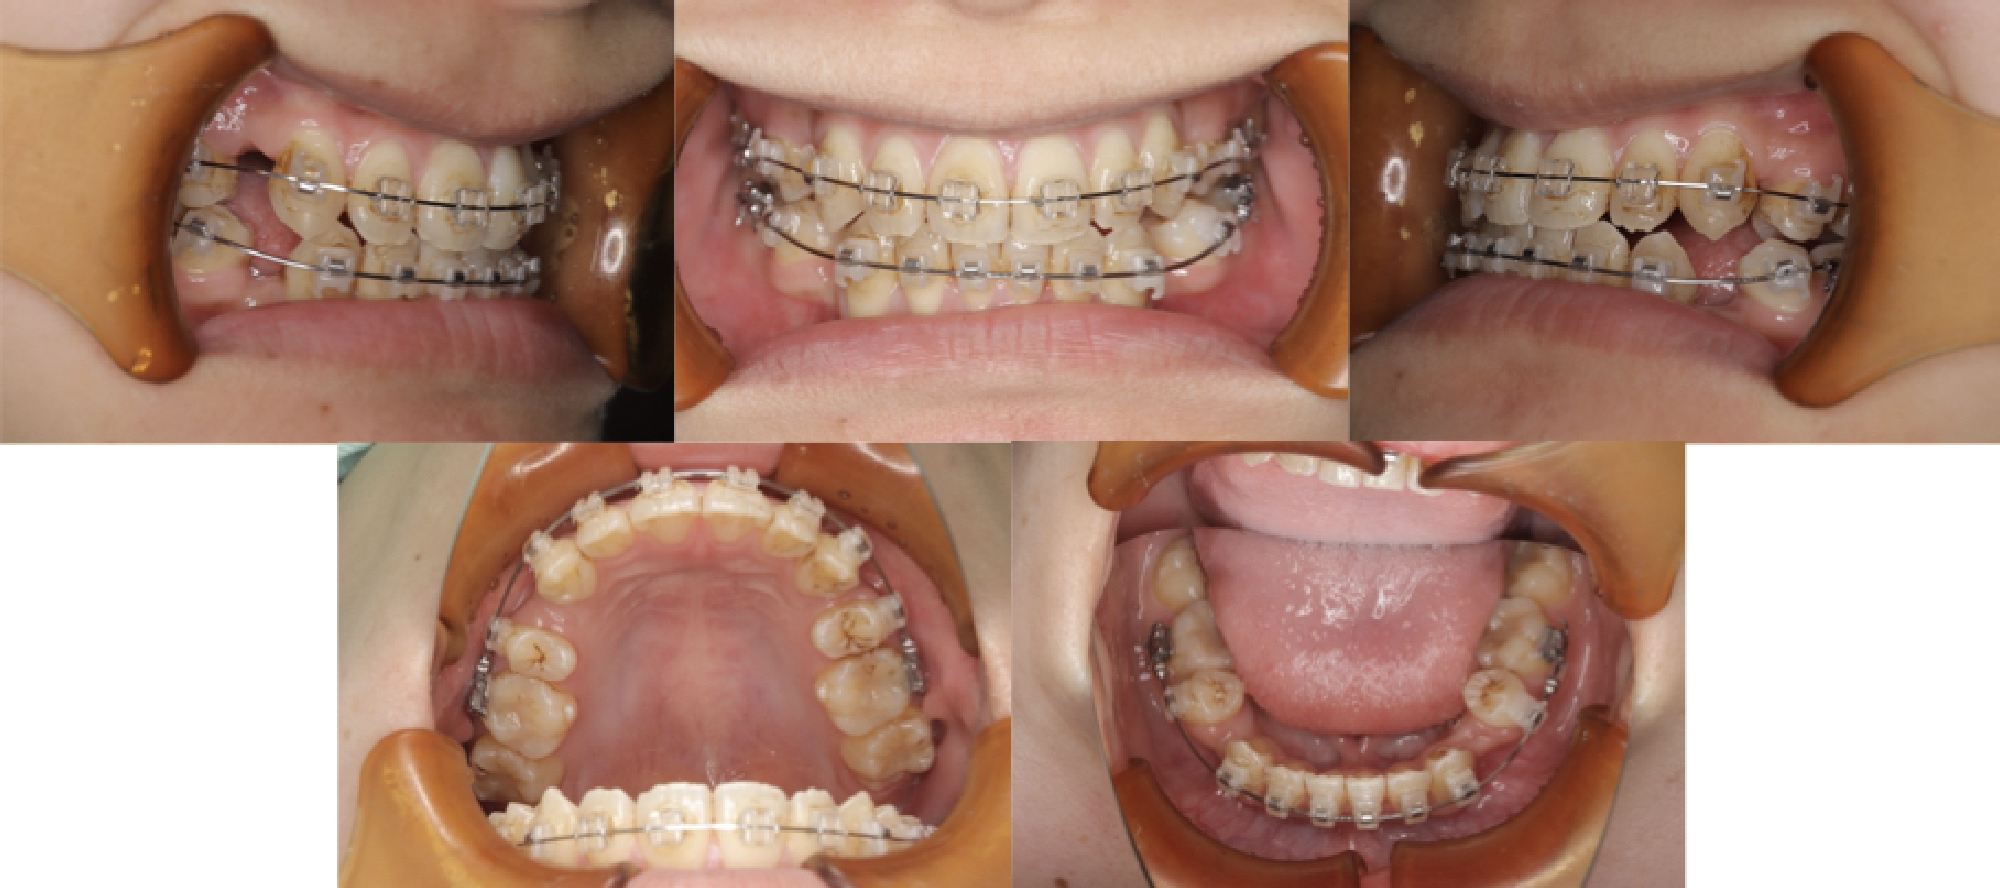

3DCTの治療例

初診時口腔内写真

治療中

治療終了時

治療が終わる頃の歯の位置は、事前に作成した3Dセットアップで想定した「骨の中で無理のない位置」とほぼ一致しています。※症例により個人差があります。